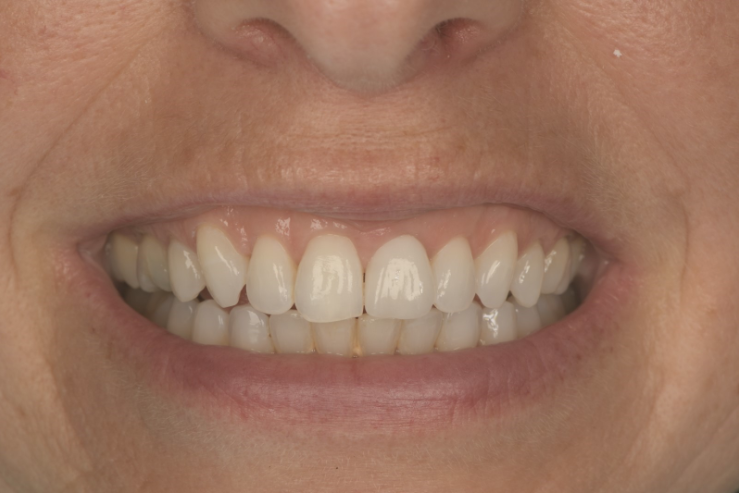

Here is a more recent case…

Not only have we honed our techniques and are using the better, modern equipment available to us, but our systems and processes allow us to work smarter, not harder.

In turn, this leaves us time to focus on working on the next one per cent improvement.